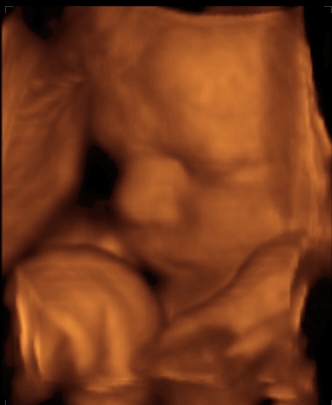

Gesicht 33. SSW

3-D-Sonographie